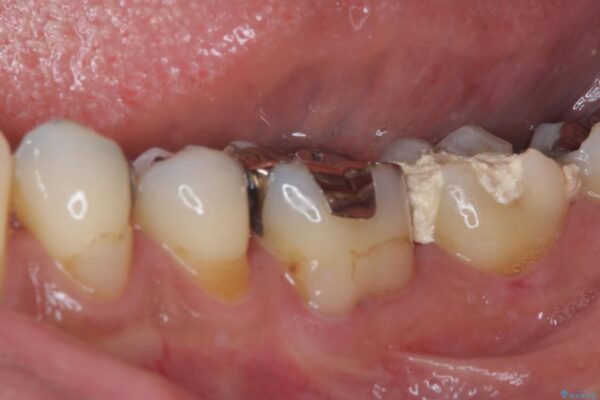

痛みを感じ近医を受診したものの、違和感が改善しないとのことで来院された患者様です。

診査をしたところ、神経組織に影響を及ぼすような大きな虫歯があることが分かりました。

虫歯が歯髄腔(神経の部屋)に達している可能性が非常に高かったため、炎症を起こしている神経組織を部分的に切除し、歯根部分の神経組織を保存する治療法が望ましいと考えられました。

治療前

• 治療をしても違和感の続く奥歯 神経を極力残した虫歯治療 治療前画像